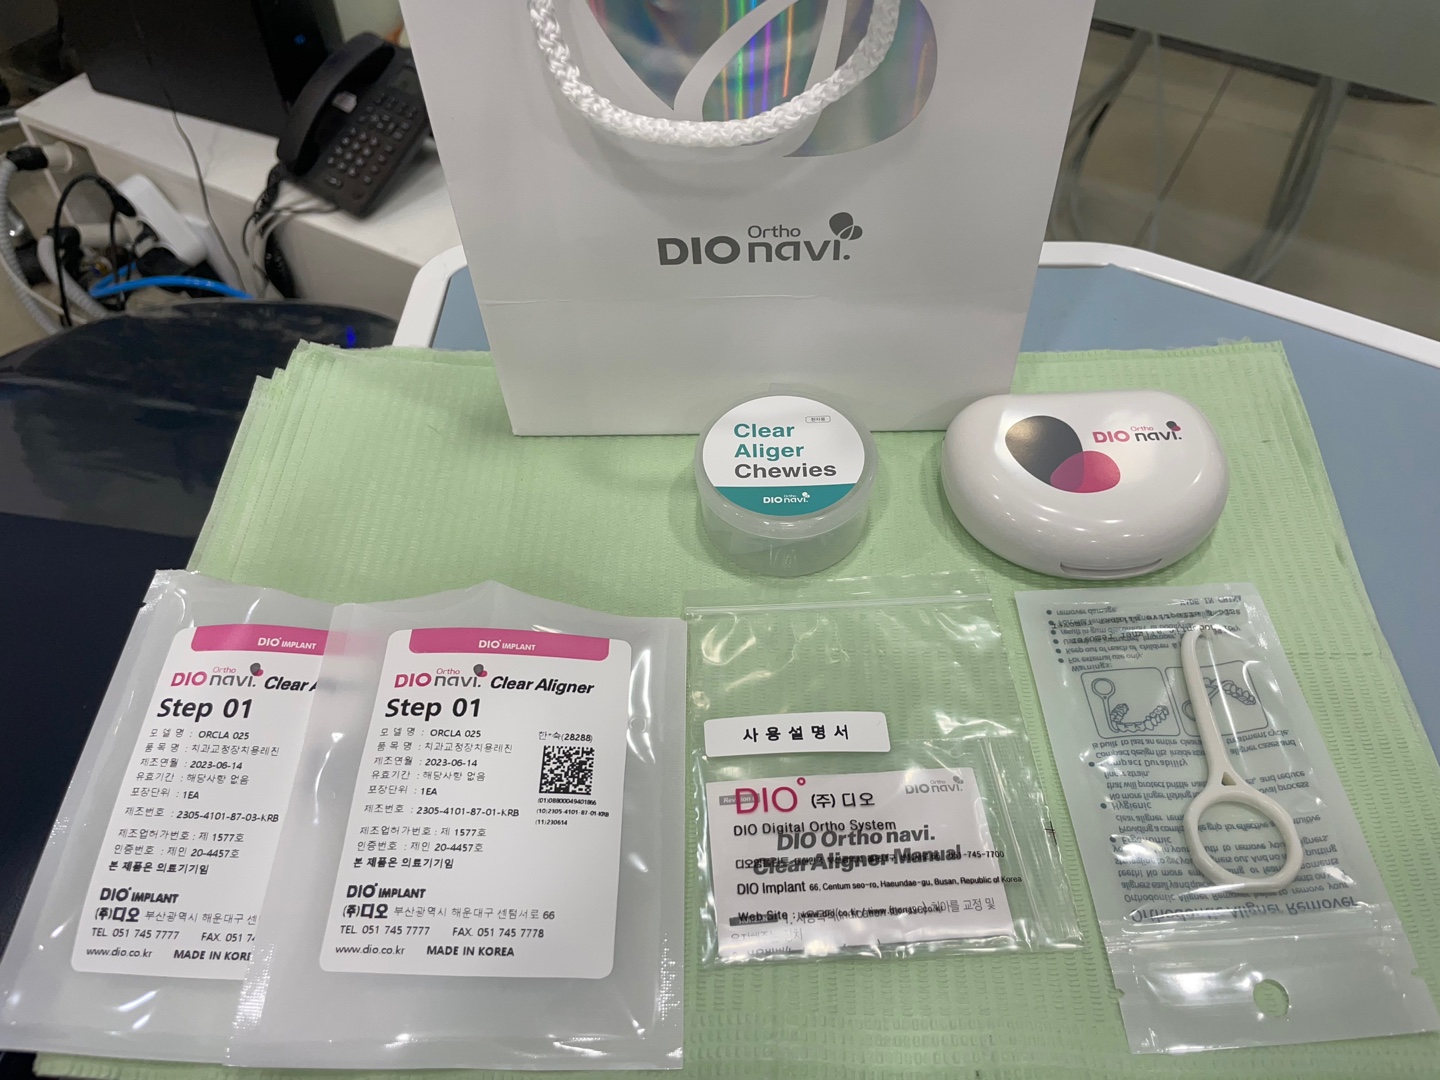

약 10일 뒤면 모든 장치들이 한꺼번에 만들어져서 본원에 오게 됩니다.

아래는 도착한 장치물입니다.

이젠 배가 출발했습니다. 약 8개월 뒤면 목적지에 도착할 것입니다. 환자분이 원하시는 곳에 정확히 도착할 수 있도록 병원은 최선을 다하겠습니다.